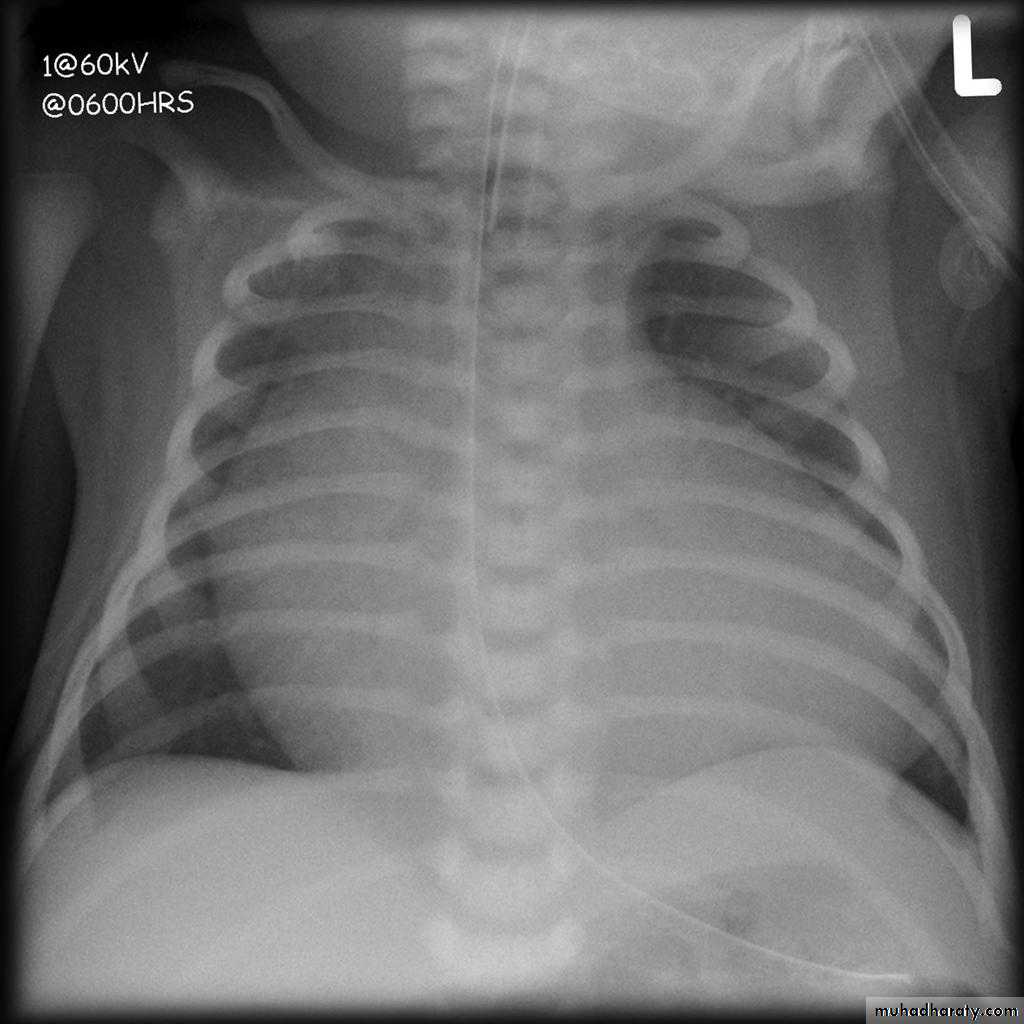

19.Egg on side heart y(Transposition f great vessels )

CXR of a child PA view shows:cardiomegaly with a cardiac contours classically described as appearing like an "egg on a string "

apparent narrowing of the superior mediastinum as result of the aortic and pulmonary arterial configuration.